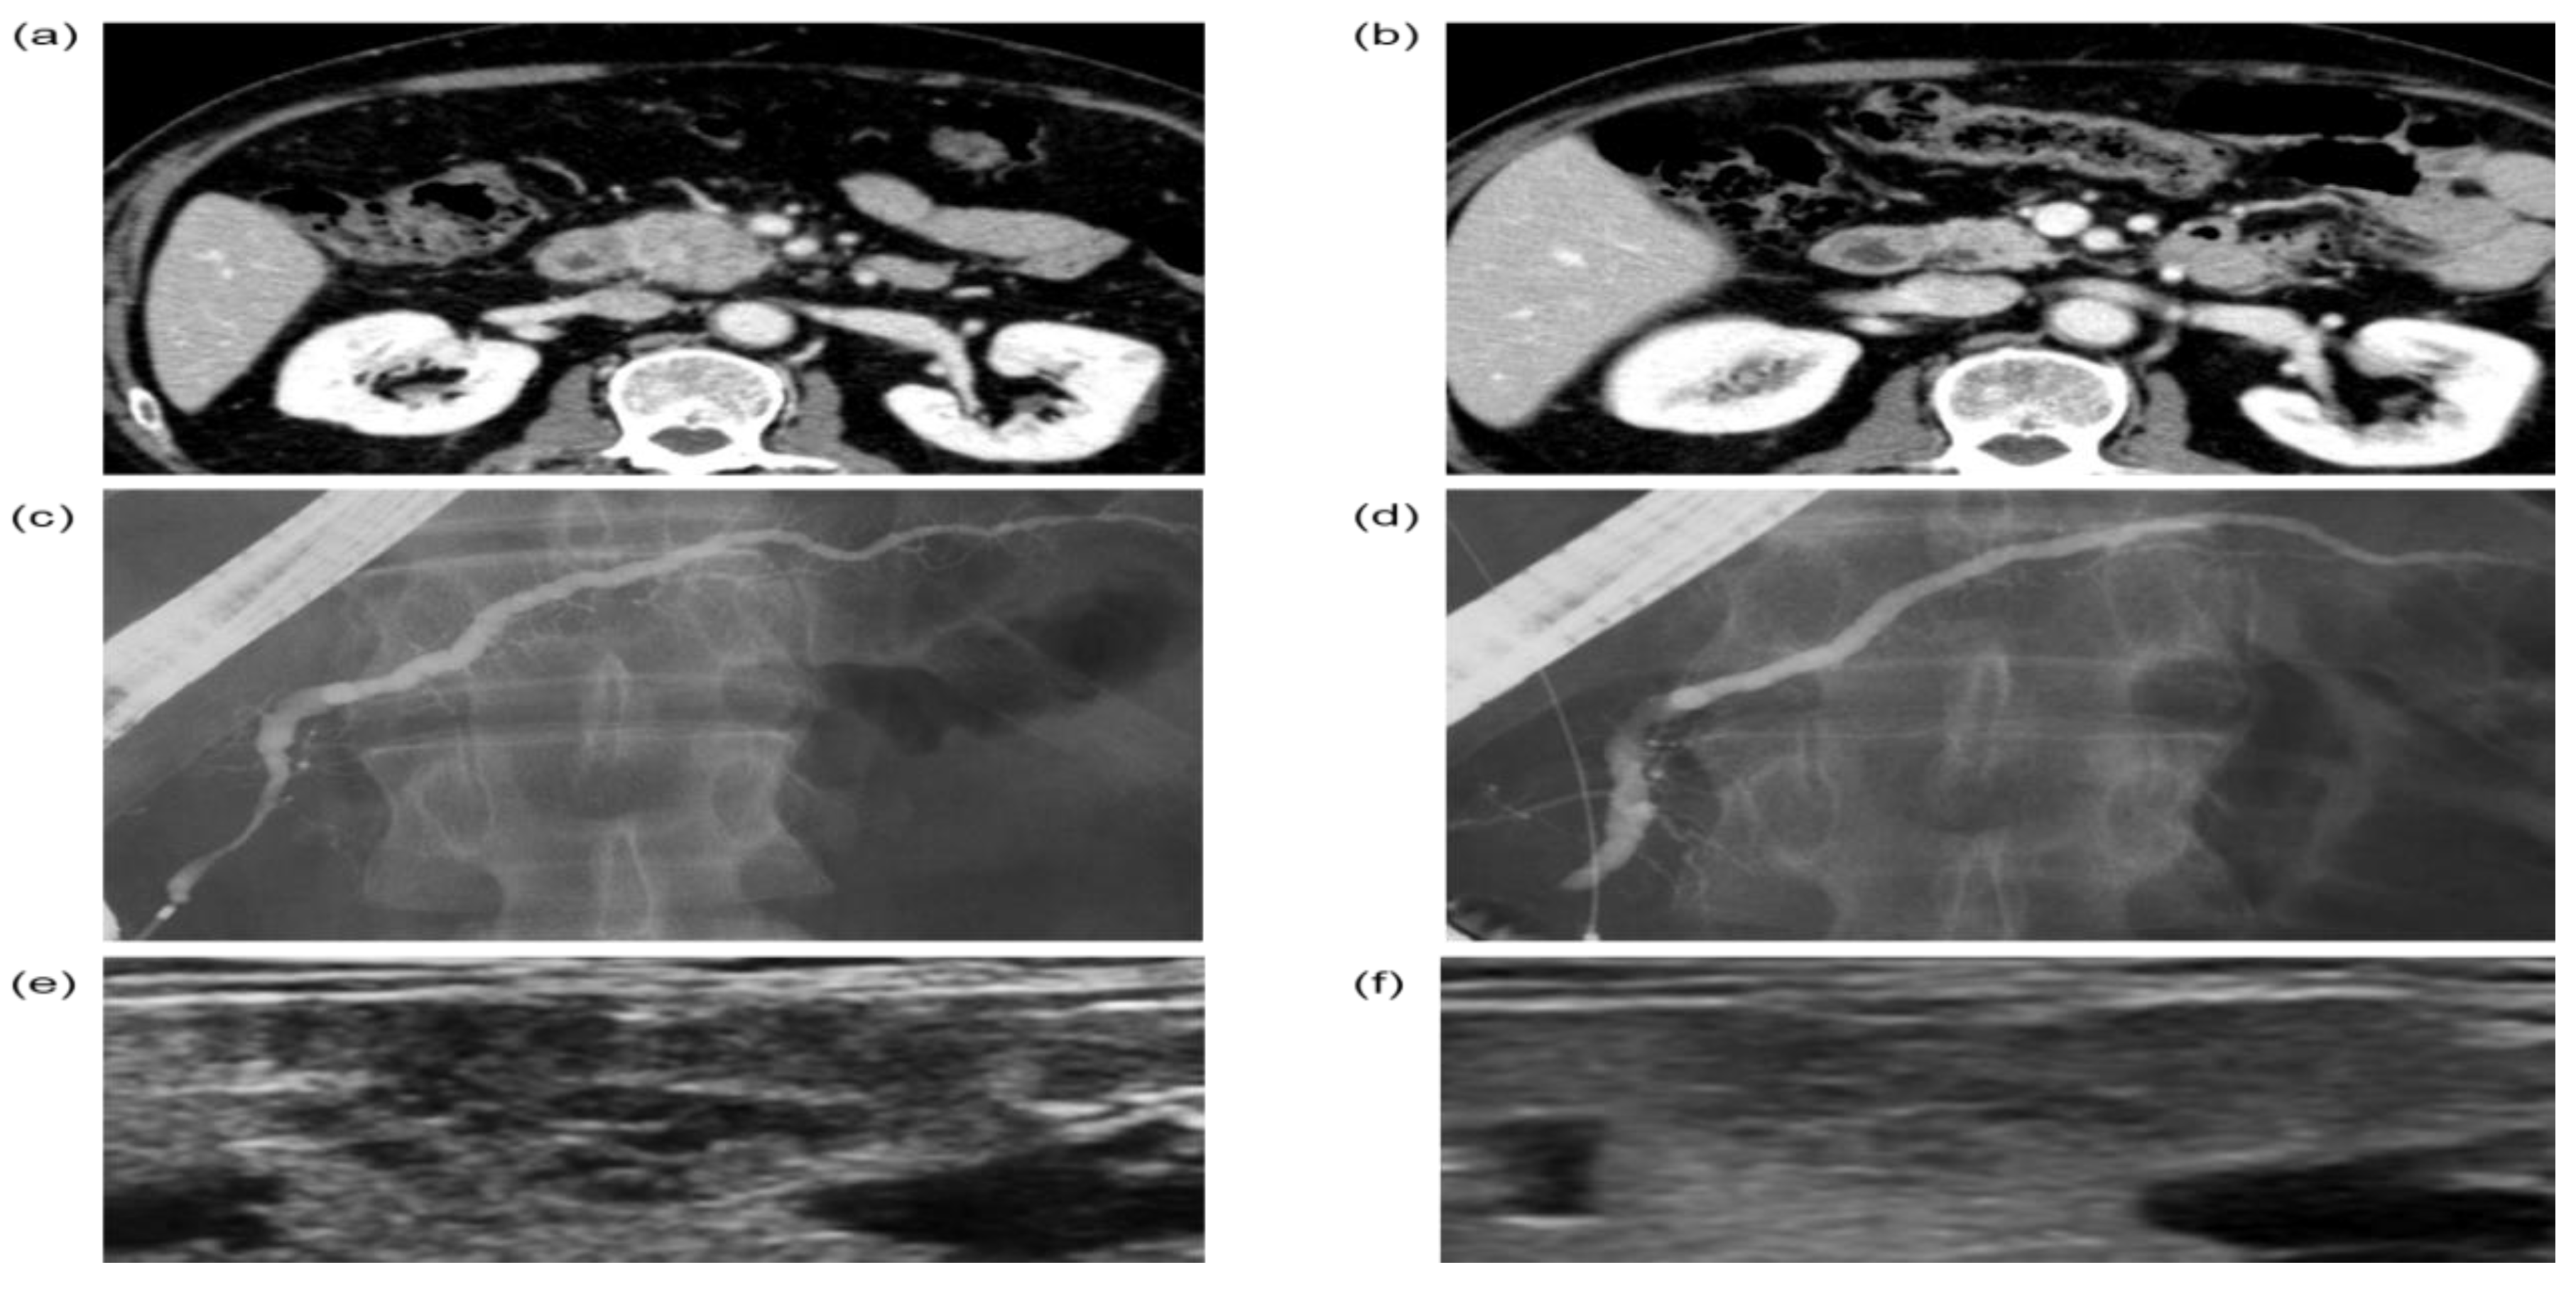

3.5. A Representative Case in Which US Findings of SGs Might Be Useful